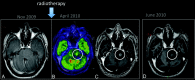

Fig 3.

Pseudoprogression. A 25-year-old man with a low-grade glioma in the left aspect of the pons (A, arrow) was treated with only RT. PET-MR imaging (B) showed hypermetabolism in the enhancing portion of the lesion (C). An MR imaging examination performed 1 month later (D) shows a reduction in the enhancing portion of lesion.